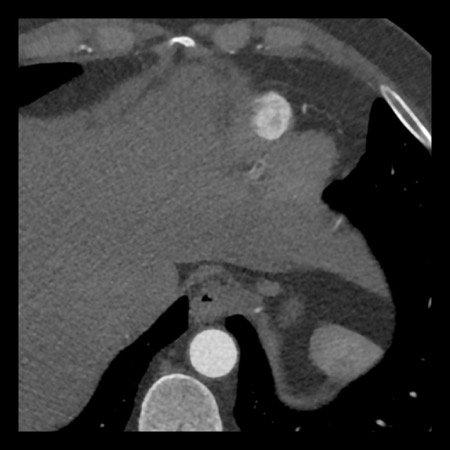

Continue with the next images of the same patient…

Same patient.

Double-oblique (A) and volume-rendered (B) images of the LAD showing the

location and the length of the plaque.

Also, the stenosis in the D2 branch of the LAD can be appreciated on the volume

rendered reconstruction.

Due to the degree of stenosis and the presence of napkin-ring sign (visible on

axial images) this patient underwent ICA where the presence of severe stenosis

was confirmed.